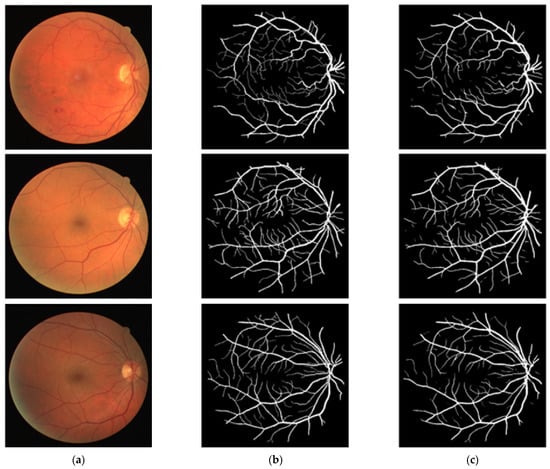

3.4. Visual Results of the Proposed Method for Vessel Segmentation

In this section, the vessel segmentation visual results are presented for the publicly available DRIVE, STARE, and CHASE-DB1 retinal image datasets. The output of the network is a binary mask that is compared with an expert annotation mask for evaluation. Figure 9, Figure 10 and Figure 11 display the visual results of the proposed method; Figure 9, Figure 10 and Figure 11 display the (a) original input image, (b) expert annotation mask, and (c) predicted mask for the proposed method.

Figure 9. Visual results of the proposed DSA-Net Using the DRIVE Dataset: (a) Original input image, (b) Expert annotation, and (c) Predicted image mask by DSA-Net.

Jpm 12 00007 g009